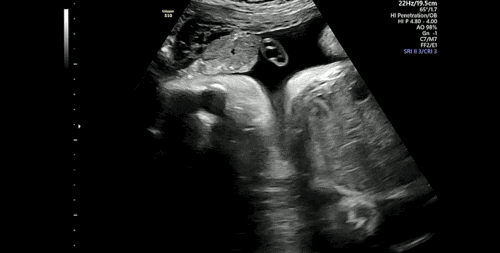

임신기록/34주차 증상 및 초음파 사진

34주차 증상 - 밤에 적게는 1번 많으면 3번정도 깨서 화장실을 간다 - 이 시기때쯤 태동이 준다고 했지만 ...